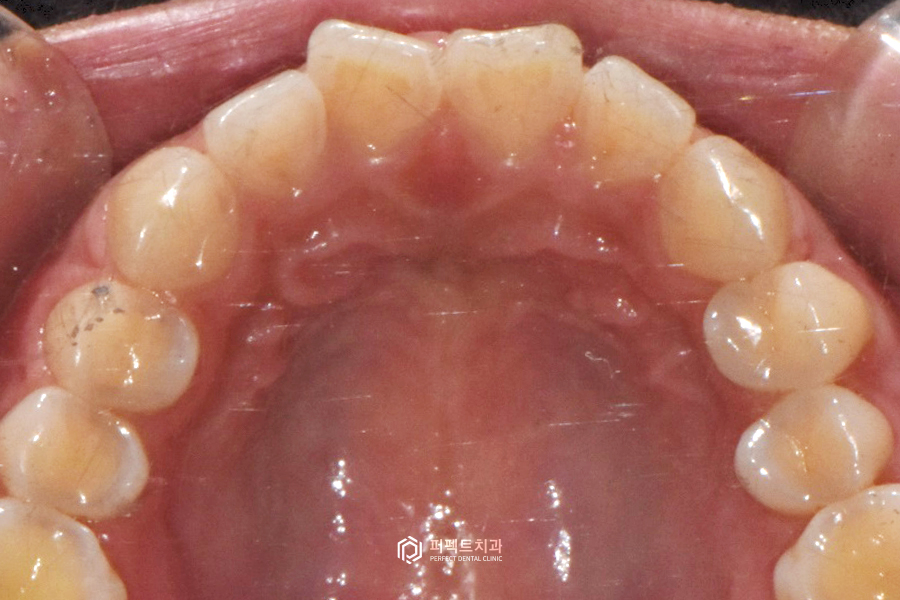

먼저 앞니의 배열을 바꾸는 부분교정 케이스를 확인해보겠습니다. 앞니가 V자로 꺾여있는 나비치아인 것을 한 눈에 알 수 있는데요. 환자분께서는 이 꺾여있는 나비치아를 둥그렇게, 정상적인 치아배열을 원하시는 상황이었습니다.

교정을 하지 않고 폴리네이트로 완성을 한 케이스를 확인해보도록 하겠습니다. 치료 전 사진을 보시면 위 환자분도 부분교정 케이스와 마찬가지로 앞니 바깥쪽 부분이 튀어나와 있는 전형적인 나비치아 케이스인 것을 확인할 수 있습니다.